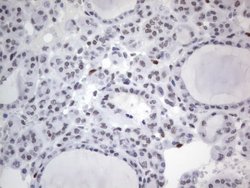

RBFOX1 Mouse anti-Human, Clone: OTI4F9, lyophilized, TrueMAB™

| Immunohistochemistry (Paraffin), Western Blot | |